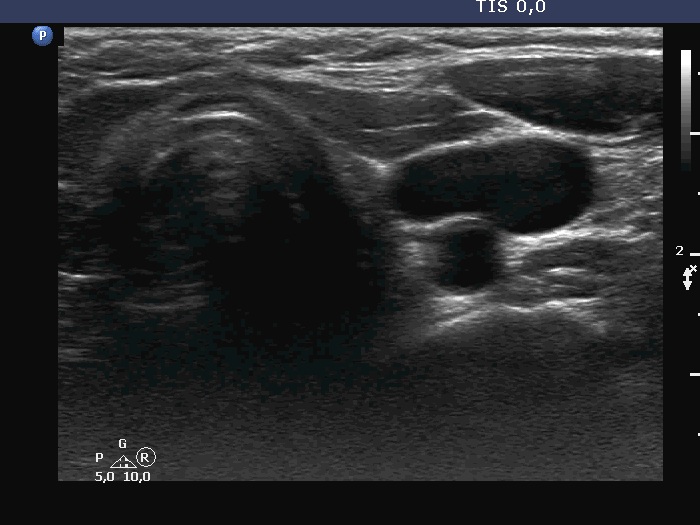

Ultrasonography. There was no thyroid tissue in the thyroid beds. Approximately 7 cm above the thyroid in the left side of the neck there were multiple, moderately hypoechoic lesions which presented tiny cystic areas. They had vascularity but did not have capsule.